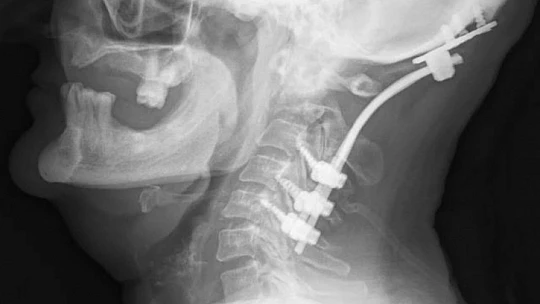

Ukrayna’da devam eden savaşta ülkede mahsur kalan Ahıska Türkleri, tahliye edilerek Elazığ’a getirilmiş ve Aşağıdemirtaş Geçici Konaklama Merkezine yerleştirilmişti. Burada yaşayan bir vatandaş, desteksiz yürüyememe ve boyun ağrıları şikayetleri ile Fethi Sekin Şehir Hastanesi Beyin Cerrahi Kliniğine müracaat etti. Hastanede ayrıntılı muayene ve tetkiklerde hastanın boynunda tümör olduğu saptandı. Beyin ve sinir cerrahisi kliniğinde başarıyla ameliyatı yapılan hasta, sağlığına kavuştu.

Beyin ve Sinir Cerrahisi Uzmanı Opr. Dr. Fatih Demir, “Boynundaki tümörün etkisiyle omurgada kırık ve açılanma gelişen hastamız ayakta durmakta güçlük çekiyor ve desteksiz yürüyemiyordu. Yaptığımız detaylı muayene ve tetkiklerle boynundaki tümörün hastadaki şikayetlere sebep olduğunu saptadık. Hastamızı ameliyat ederek baş ile boyun omurlarını sabitledik ve omuriliğe bası yapan tümörünü çıkardık. Başvurduğunda ayakta durmakta güçlük çeken ve desteksiz yürüyemeyen hastamızı yürüyerek taburcu ettik" dedi.